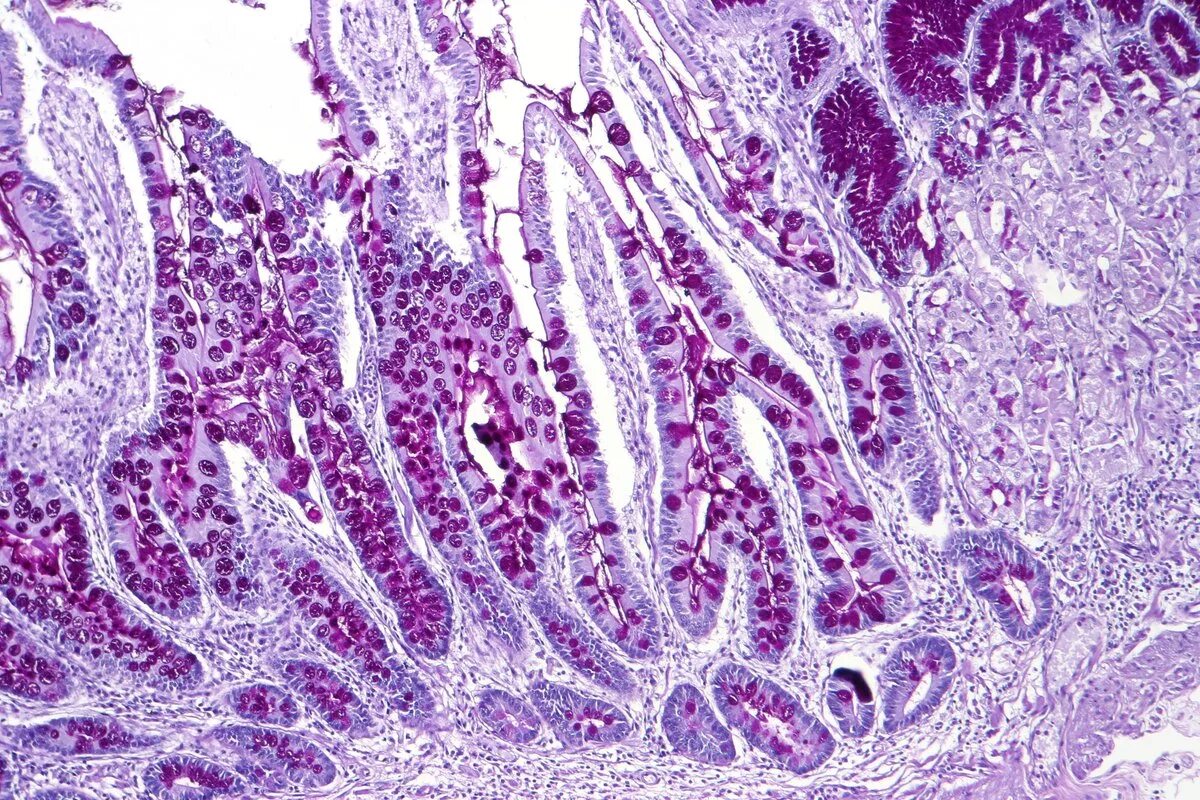

Гистология фото